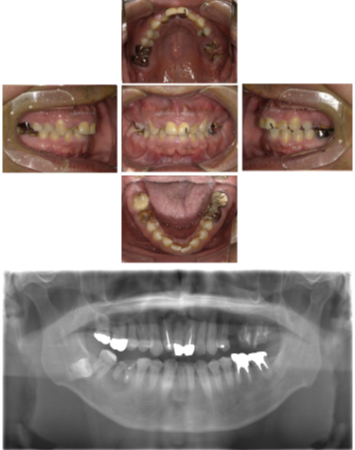

30代 女性 インプラント治療(鎮静療法)

| 年代・性別 | 30代・女性 |

| 主訴 | 口腔内かなり状態悪く、これから先しっかり噛んで食事ができるようにインプラントを入れたい。 |

| 部位 | 左上3,5,7、右下5 |

| 治療期間 | 約11ヶ月 |

| 費用 | ¥2,145,000(税込) |

| 副作用・リスク |

|